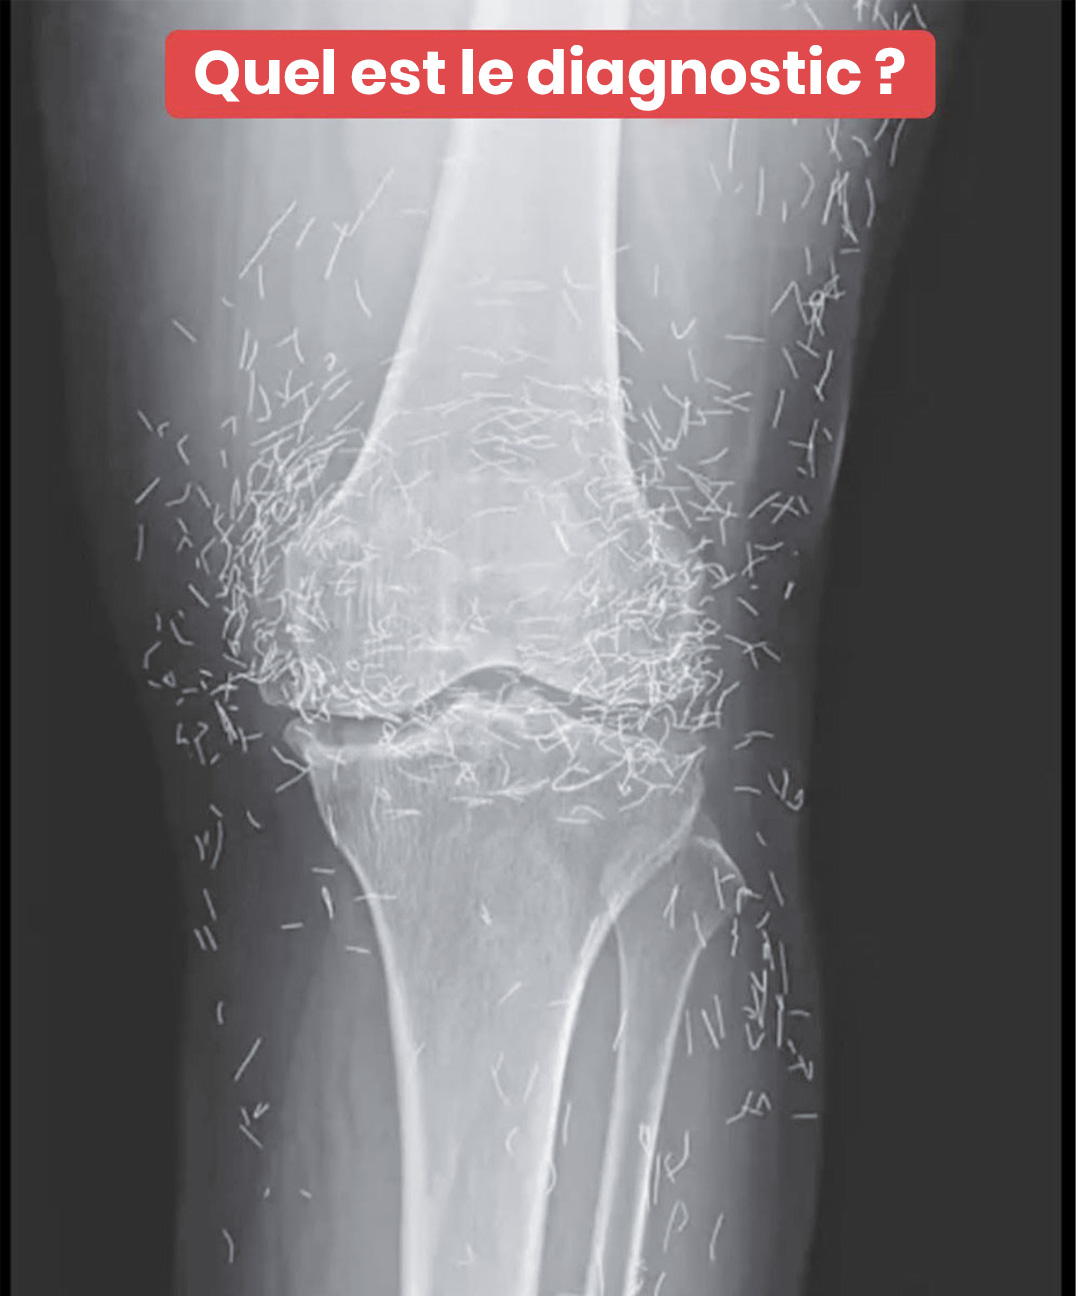

Une révélation radiographique : des aiguilles d’or cachées dans une articulation

L'examen d'imagerie d'une patiente a mis au jour une découverte médicale fascinante : des centaines de micro-aiguilles dorées logées dans ses genoux. Cette trouvaille insolite soulève des questions sur des pratiques thérapeutiques peu connues en Occident mais répandues dans d'autres cultures. Une enquête captivante sur les mystères de la médecine alternative.

C’est lors d’un examen d’imagerie médicale classique que l’équipe soignante a fait une observation surprenante : une multitude de petites aiguilles brillantes dispersées près de ses genoux. Une véritable curiosité médicale qui a suscité à la fois de l’intérêt et de la prudence. Car si l’or est bien toléré par l’organisme, la présence d’éléments étrangers dans les tissus n’est jamais sans risques.

D’après des spécialistes en radiologie, ces implants métalliques peuvent masquer certaines zones sur les radiographies, rendant parfois plus difficile le diagnostic d’autres problèmes. Plus inquiétant encore, ils empêchent souvent la réalisation d’une IRM : le risque que les aiguilles se déplacent sous l’effet du champ magnétique est réel, avec un danger potentiel de blessure des tissus environnants.